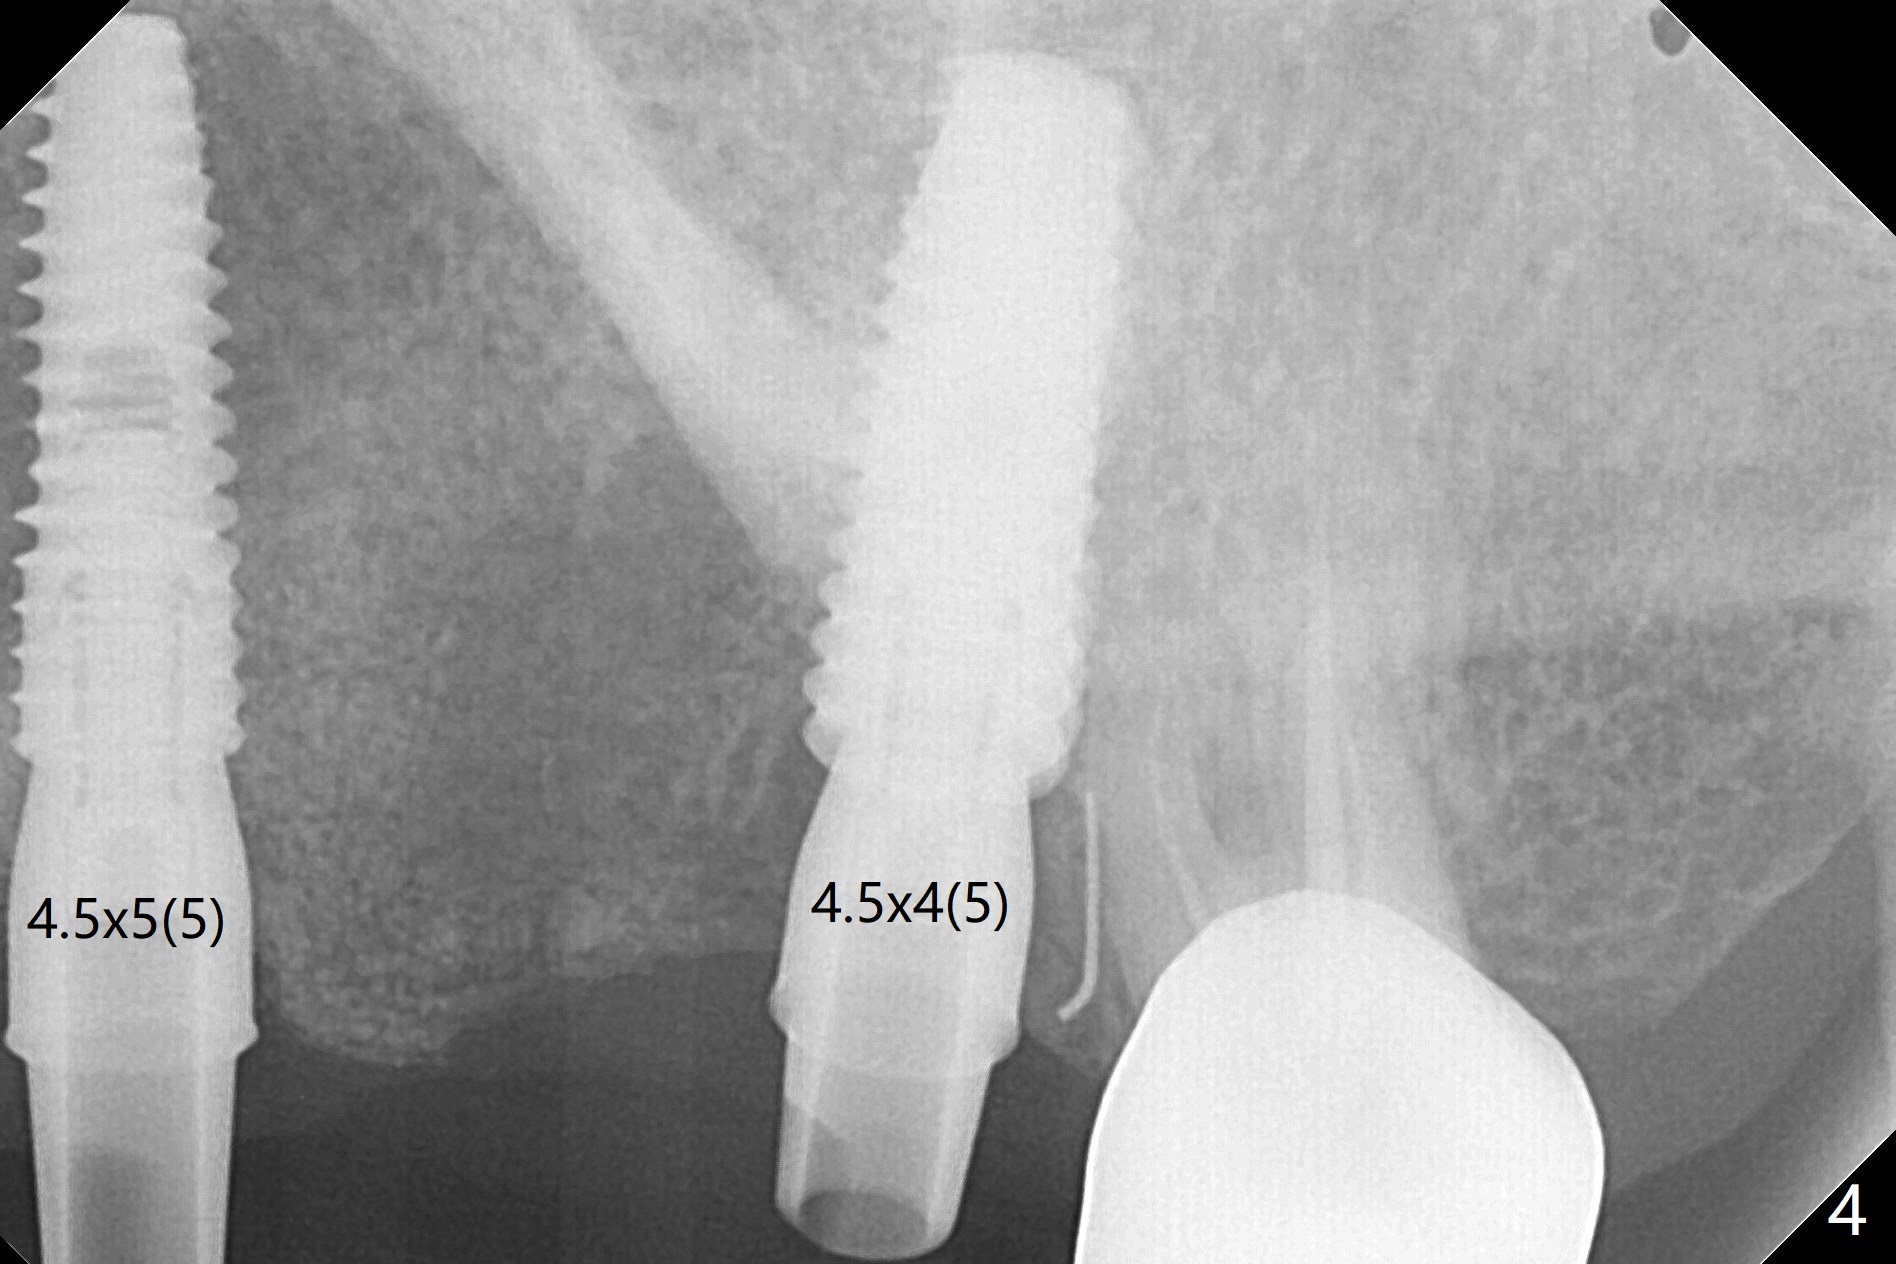

A 55-year-old woman had Hiossen implants (4x13, 5x13 mm) placed at #12 and 14 in China > 6 months (Fig.1,2). The fixtures are placed deep and un-parallel mesiodistally. After SRP UL, the implant at #12 is uncovered, followed by 4.6 and 5.5 mm profile drills and 5.5x7 mm IS healing abutment. The healing abutment at #14 is changed from 5x7 mm to 6.8x7 mm for easy impression later on. Due to coronavirus, the patient returns 8 months later. Oral hygiene is poor. The gingival cuffs at #12 and 14 are erythematous and edematous. UF cemented abutments have to be placed (Fig.3-5) because of equi-gingival fracture of #3 and 4 splinted crowns. In fact the straight abutments are not parallel buccopalatally. Buccoocclusal reduction is done at #12 for provisional FPD. SRP will be performed with #11 DL composite prior to impression.